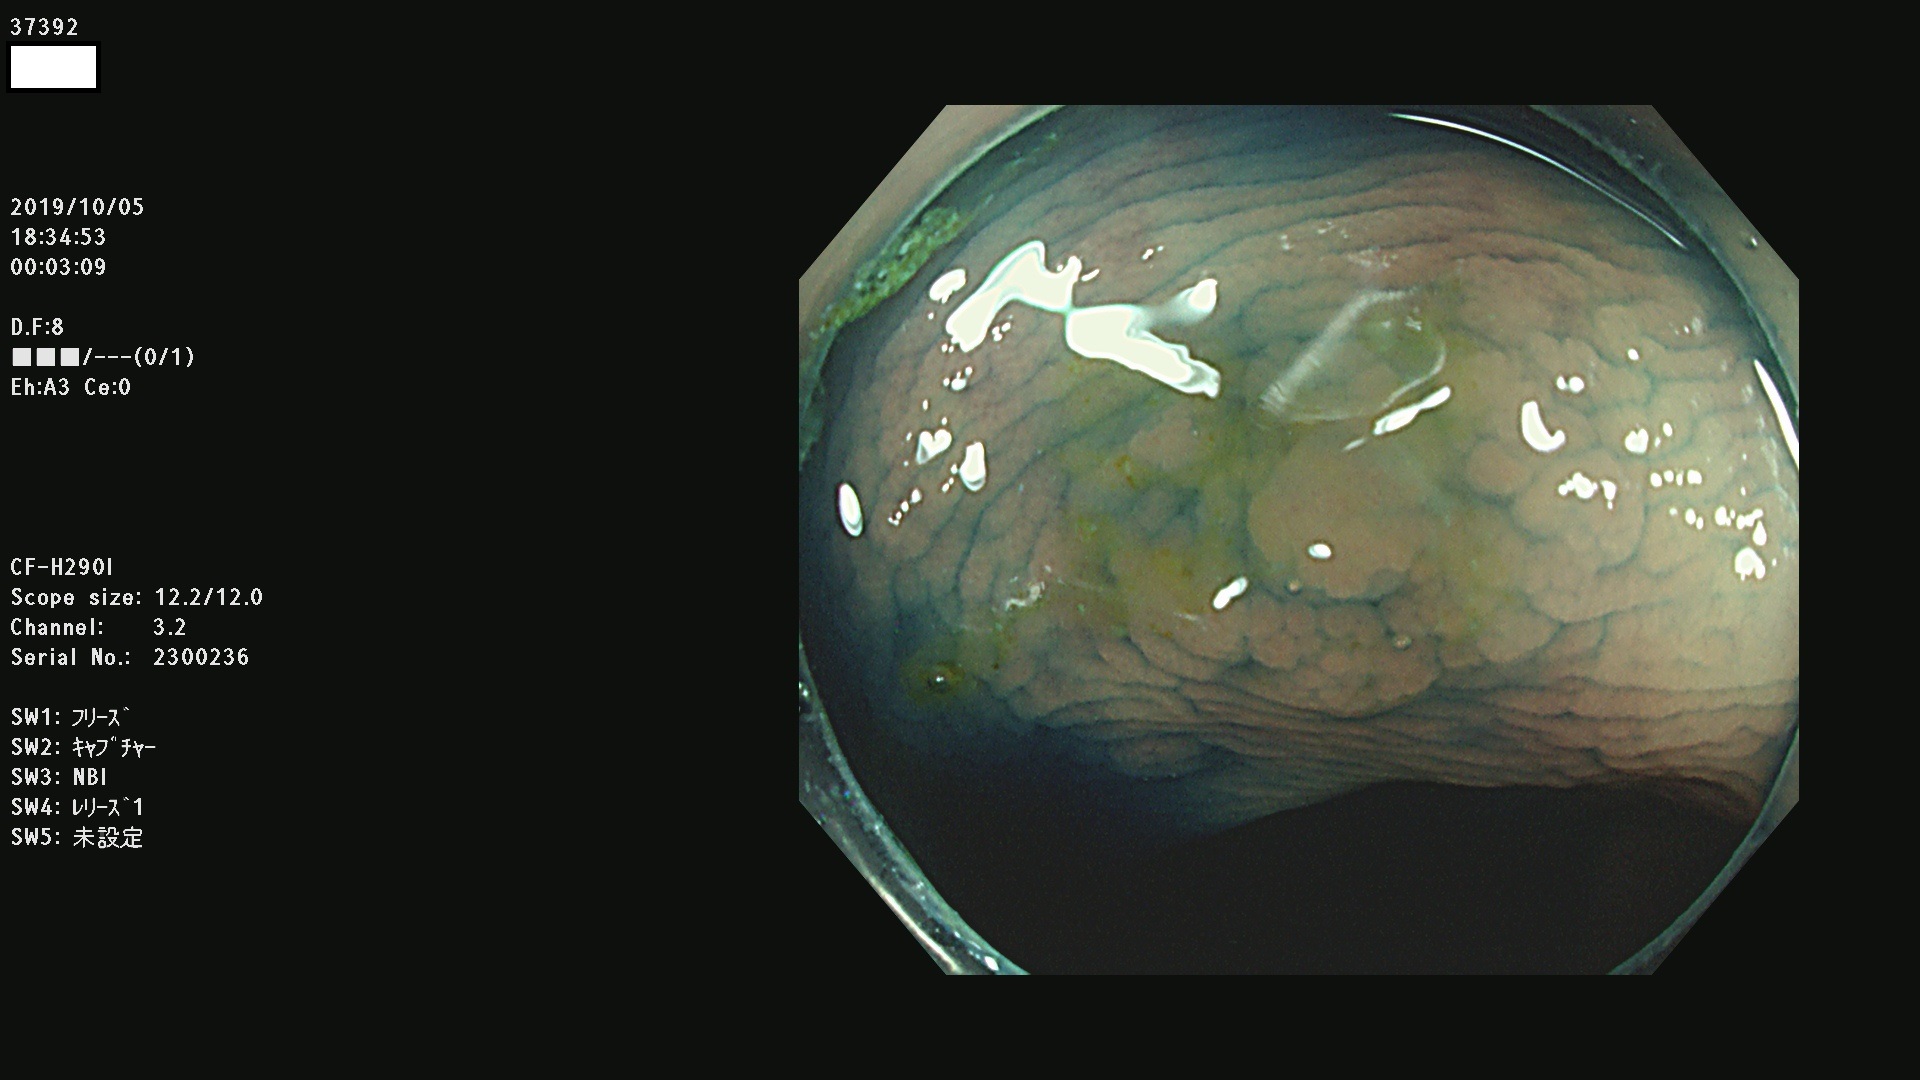

37300(SSAPのみ) 37301 37303 37304 37306 37307 37308 37309 37312 37313 37315(SSAPのみ) 37316 37317(SSAPのみ) 37319 37321(SSAPのみ) 37322 37323 37324 37325 37326 37328(SSAPのみ) 37329 37330 37331 37332(SSAPのみ) 37333 37334 37336 37337 37338 37340 37342 37343(SSAPのみ) 37344 37345 37346 37347 37348 37352(SSAPのみ) 37353 37354 37355 37356 37358 37360 37361(SSAPのみ) 37362 37363 37366 37367 37369 37370 37371 37372(SSAPのみ) 37375 37376 37377 37380 37381(SSAPのみ) 37382 37383 37384 37385(SSAPのみ) 37386 37387 37388 37389 37390 37392(SSAPのみ) 37393 37394 37395 37396(SSAPのみ) 37397 37398(SSAPのみ) 37399

発見困難で危険性の高い平坦型病変(上記100名より抽出) )